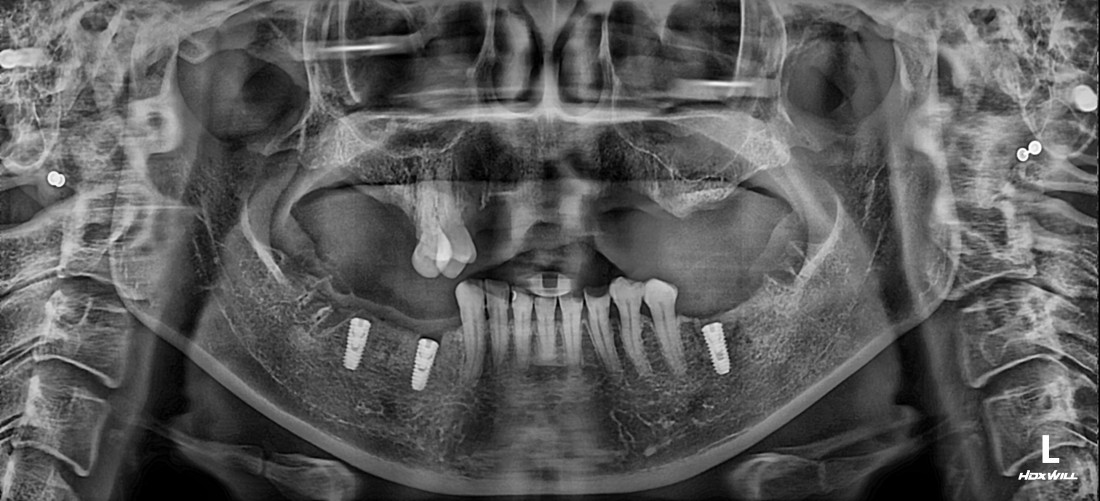

광주 상악임플란트 치과는

전체 임플란트 수술도

단 2번의 수술만으로

완성합니다.

광주 상악임플란트 치과에서는

위 / 아래 전체 임플란트를

붓기, 출혈, 통증을 최소화할 수 있는

디지털 가이드 임플란트 수술방법으로

단 2번의 수술만으로 완성하고 있습니다.

4층 자체 치아기공소를 운영하고 있으며

보철물 디자인 퀄리티를

굉장히 중요하게 생각하고 진료하기 때문에

자연치아만큼 예쁘면서도

잘 씹어지는 광주 상악임플란트 진료를

보장할 수 있습니다.